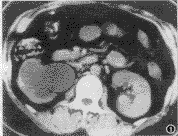

CT扫描见右肾重度积水,肾皮、髓质萎缩变薄(图1),近段输尿管扩张,至腰4 椎体水平扩张的输尿管截断,形成一约2.0cm×1.6cm×0.8cm大小的不规则形软组织样肿块(图2),CT

值45HU±,边缘模糊、毛糙,并见多束条索状结构延伸至右侧腹壁,结合病史,CT诊断右输尿管瘢痕形成继发肾积水,肾无功能。

行右肾及部分输尿管切除术,病理诊断右输尿管瘢痕形成,右肾积水,无功能。

讨论 本病极少见,属体外碎石治疗术的严重并发症,从CT上主要与输尿管肿瘤相鉴别,结合病史及CT表现不难鉴别。